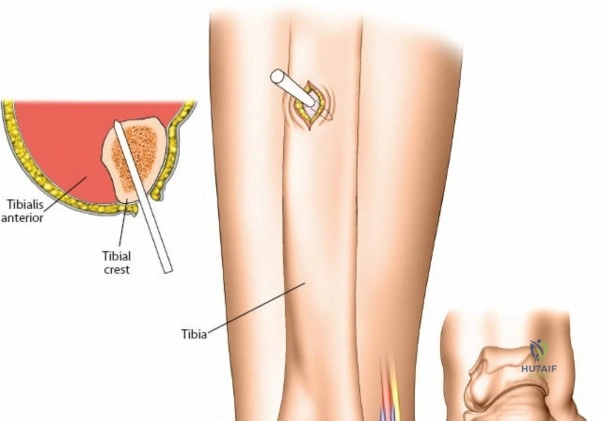

Ulna External Fixation

The ulna is straightforward due to its subcutaneous border.

- Palpate the subcutaneous crest of the ulna.

- Make stab incisions over the planned pin sites (typically two proximal and two distal to the fracture).

- Dissect bluntly to the periosteum.

- Place the tissue sleeve and drill perpendicular to the longitudinal axis of the bone.

- Insert 4.0 mm pins bicortically.

- Connect the pins with an 8 mm rod and reduce the fracture.